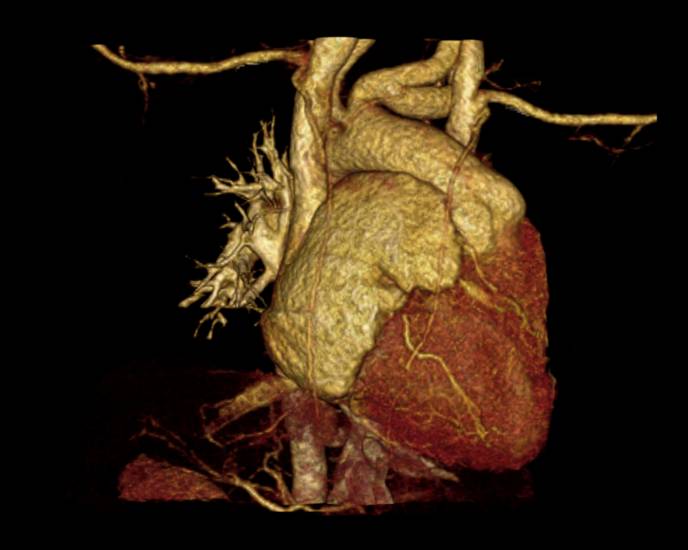

M/49, Severe dyspnea and Jaundice

Heon Lee, Department of Radiology, Soonchunhyang University Hospital Bucheon